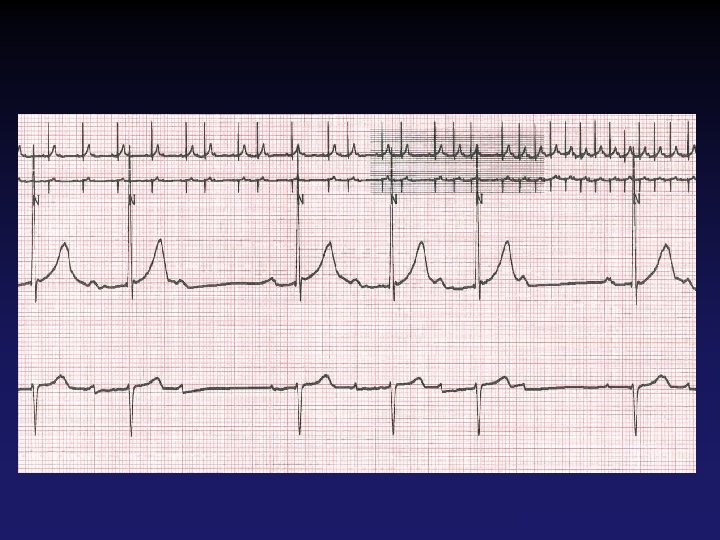

PSVT • • • Rate? Regularity? P waves? PR interval? QRS duration? Interpretation? 74 148 bpm Regular regular Normal none 0. 16 s none 0. 08 s Paroxysmal Supraventricular Tachycardia Tehran Arrhythmia Center

Paroxysmal Supraventricular Tachycardia (PSVT) • Usually at a rate of 150 -250 bpm • No organic heart disease in the majority • Presentations – Palpitations – Chest discomfort, dyspnea, lightheadedness – Frank syncope – SCD Tehran Arrhythmia Center